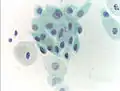

Micrograph of a Pap test showing a low-grade intraepithelial lesion (LSIL) and benign endocervical mucosa. Pap stain.

Normal squamous epithelial cells in premenopausal women- Atrophic squamous cells in postmenopausal women

- Normal endocervical cells should be present into the slide, as a proof of a good quality sampling